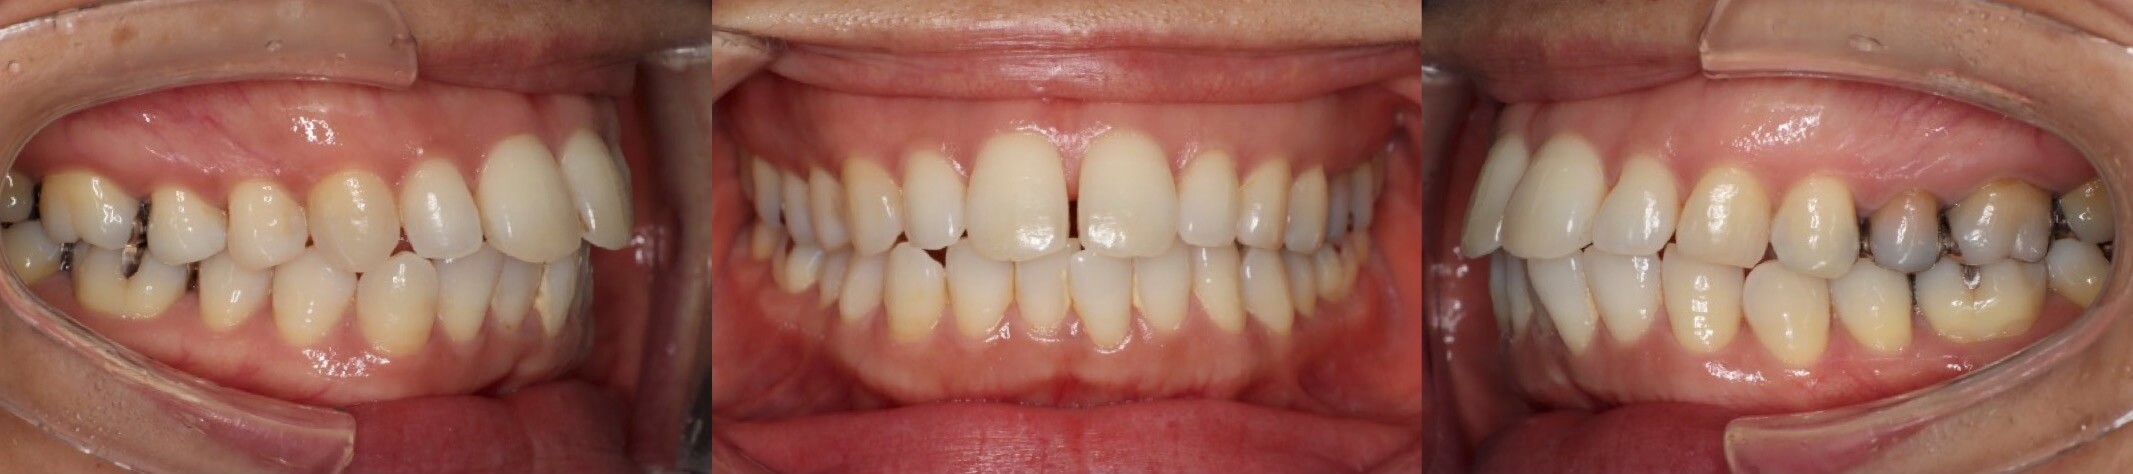

46歳女性・唇側矯正装置・抜歯

<症例概要>

主訴:前歯と口元の突出

年齢・性別:43歳女性

住まい:千葉県佐倉市

症状:叢生・上下顎前歯唇側傾斜

治療方針:上左右5番・下左右4番(計4本)

治療装置:唇側矯正装置

固定装置:ナンスホールディングアーチ

治療期間:3年

リテーナー:下フィックス+上下クリアタイプ

治療費用:968,000(税込)

代表的副作用:痛み・治療後の後戻り・歯根吸収・歯髄壊死・歯肉退縮

▶︎その他の副作用

前歯の突出のため口が閉じづらいことを気にされていて矯正治療を希望された患者さんです。年齢的に抜歯を行うか迷ったのですが、患者さんの主訴を優先して抜歯矯正により前歯を後方移動させました。抜歯部位については、上の歯並びは治療歯である第二小臼歯(5番)を選択しています。その分、治療期間は3年を超えてしまったのですが、理想的な横顔になりました。